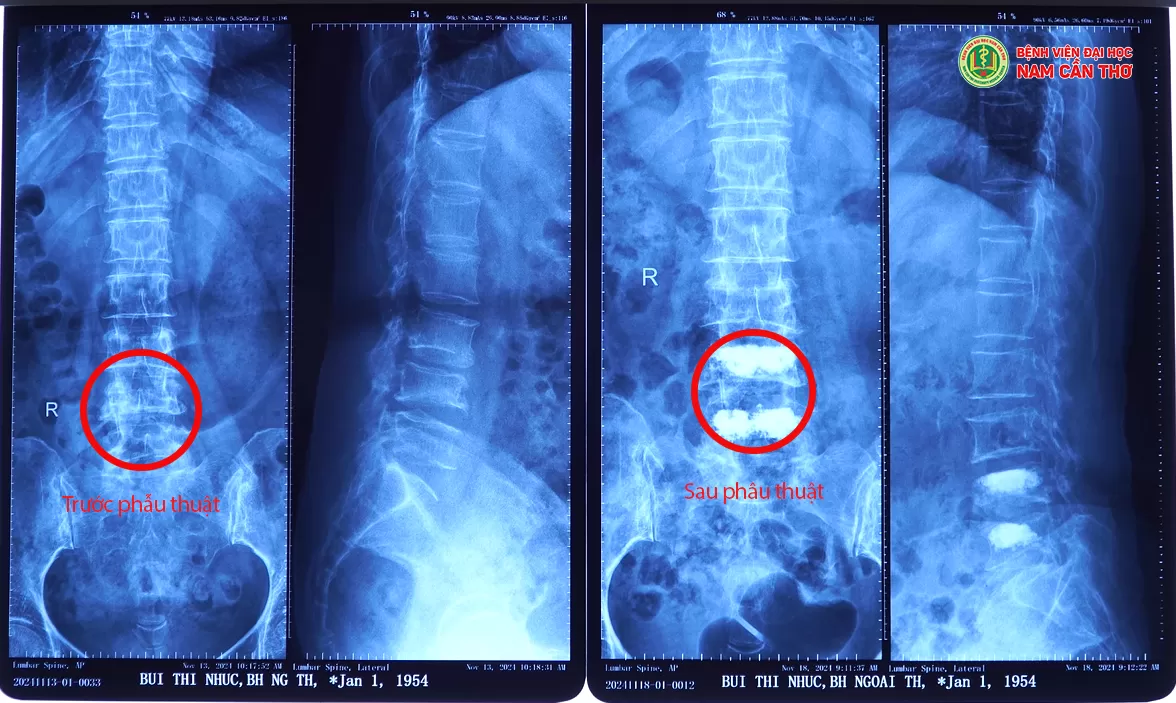

NỘI SOI TẠO HÌNH THÂN ĐỐT SỐNG VÀ LẤY NHÂN ĐỆM CHO CỤ BÀ 70 TUỔI

☘️Tại đây, bệnh nhân được thăm khám kỹ lưỡng, được chỉ định chụp MRI và thực hiện các cận lâm sàng cần thiết. Kết quả chụp MRI cho thấy xẹp thân sống L3, L4, L5 và thoát vị đĩa đệm đốt sống L4L5,L5S1. Bệnh nhân được tư vấn nhập viện điều trị, qua quá trình thăm khám kỹ lưỡng và hội chẩn chuyên khoa, các bác sĩ đưa ra phương án phẫu thuật bơm cement sinh học tạo hình thân sống L4, L5 và phẫu thuật nội soi lấy nhân thoát vị đĩa đệm L4L5.

Bác sĩ CKI Lý Tấn Phát, Bác sĩ CKI Thông Minh Vừa – Khoa Ngoại tổng hợp, cùng Ê-kíp bác sĩ đã tiến hành phẫu thuật nội soi lấy nhân đệm cột sống thắt lưng qua đường liên bản sống và tạo hình thân đốt sống bằng bơm cement sinh học qua cuống cho bệnh nhân. Được biết đây là 2 phương pháp kết hợp cùng lúc và được chỉ định trong điều trị thoát vị đĩa đệm kèm lún xẹp đốt sống có chèn ép thần kinh. Đặc biệt đối với bệnh nhân lớn tuổi có nhiều bệnh nền nội khoa thì phương pháp này được xem là phương pháp tối ưu, an toàn và mang lại hiệu quả cao. Hiện sức khỏe bệnh nhân được hồi phục, ổn định và đã được xuất viện.